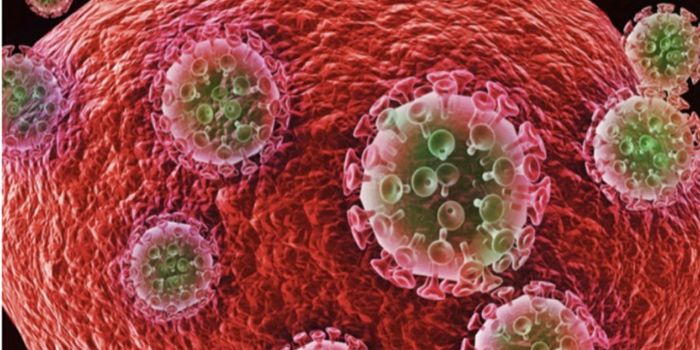

NOV 30, 2021ImmunologyHIV is a master of disguise. Once the virus enters the body, it has a number of sophisticated mechanisms through which i ...

NOV 22, 2021MicrobiologyThough treatments are available, there is no cure or vaccine from HIV, which impacts about 38 million people worldwide. ...